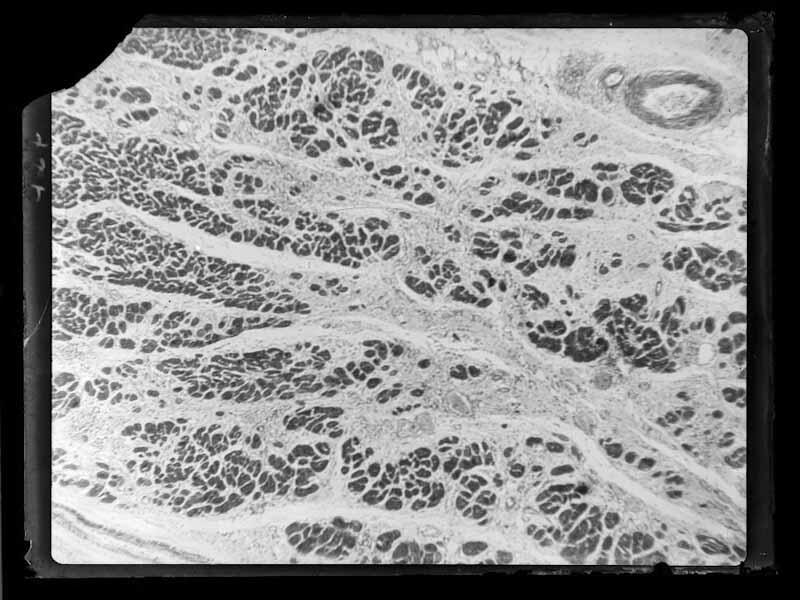

Fotomicrografia

Documentos iconográficos: 1 item (negativo de vidro p&b 9x12 cm)

Solicitação não identificada

Notação anterior: IOC-V-III-3385